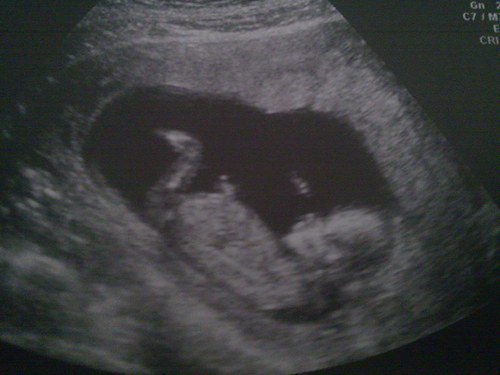

Gebelikte Hafta Hafta Ultrason Görüntüleri

Bebeğinizin başından poposuna olan mesafesi 70 mm’ye ulaşmıştır. Sinir sistemi gelişime devam etmektedir. Hatta bir takım refleksler de gelişmiştir. Bebeğin beslenmesi tamamen plasenta ve göbek kordonu üstlenmiştir ve bu haftanın başı itibari ile düşük yapma ihtimaliniz önemli ölçüde azalmıştır. Yani bebek artık annesine ve hayata çok daha sıkı tutunmaktadır.

Bu hafta sonunda bebeğinizin boyu 9 cm. ve ağırlığı tam 26 gram!

Bu dönemde genital tüberkül ("tepe") adı verilen yapının ultrasonografideki duruşuna göre (erkek bebeklerde yukarı doğru, kız bebeklerde vücuda paralel) cinsiyet konusunda bir fikir edinilmesi mümkün olsa da çoğu doktor cinsiyeti net olarak görene kadar bilgi verme konusunda isteksizdir. Halk arasında "doktorların bebeğin kemik yapısına bakarak cinsiyeti görebildikleri" konusunda yanlış bir inanç mevcuttur. Kemik yapısı ile cinsiyet arasında bir bağlantı yoktur.